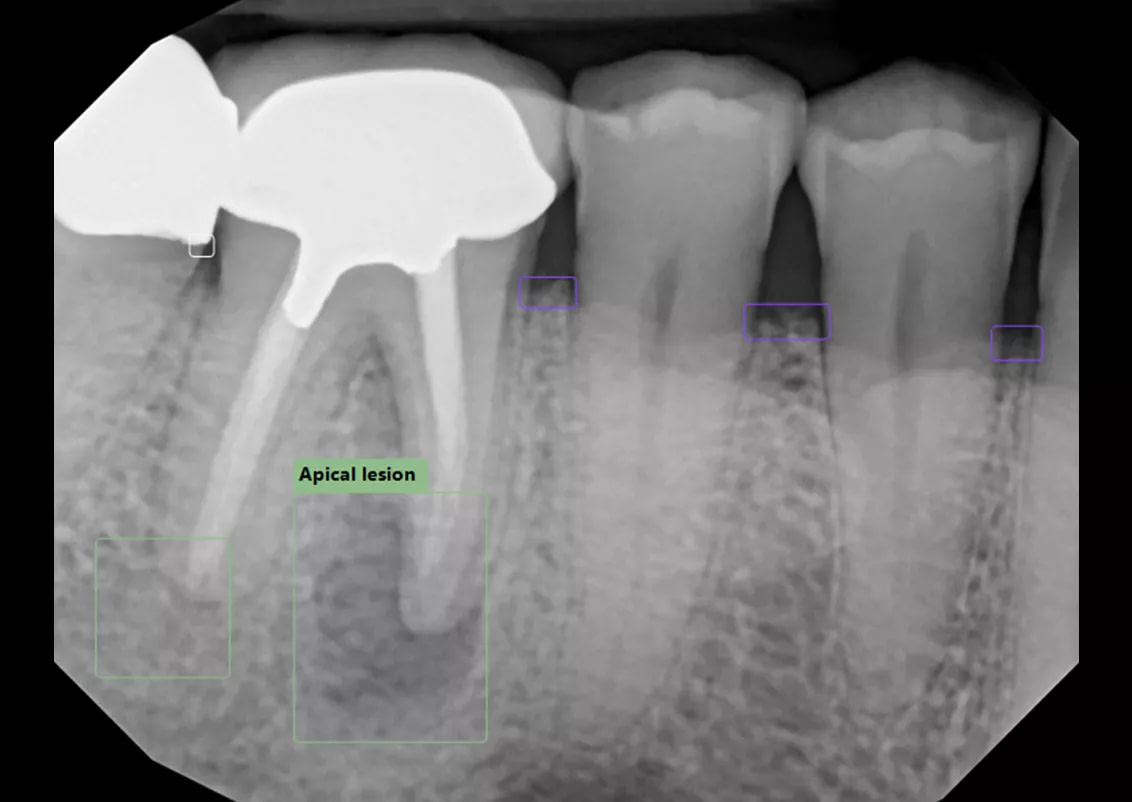

- Automatically file and organize radiographs

- Detect caries, calculus, bone loss, and other pathologies

- Trace nerve canals automatically